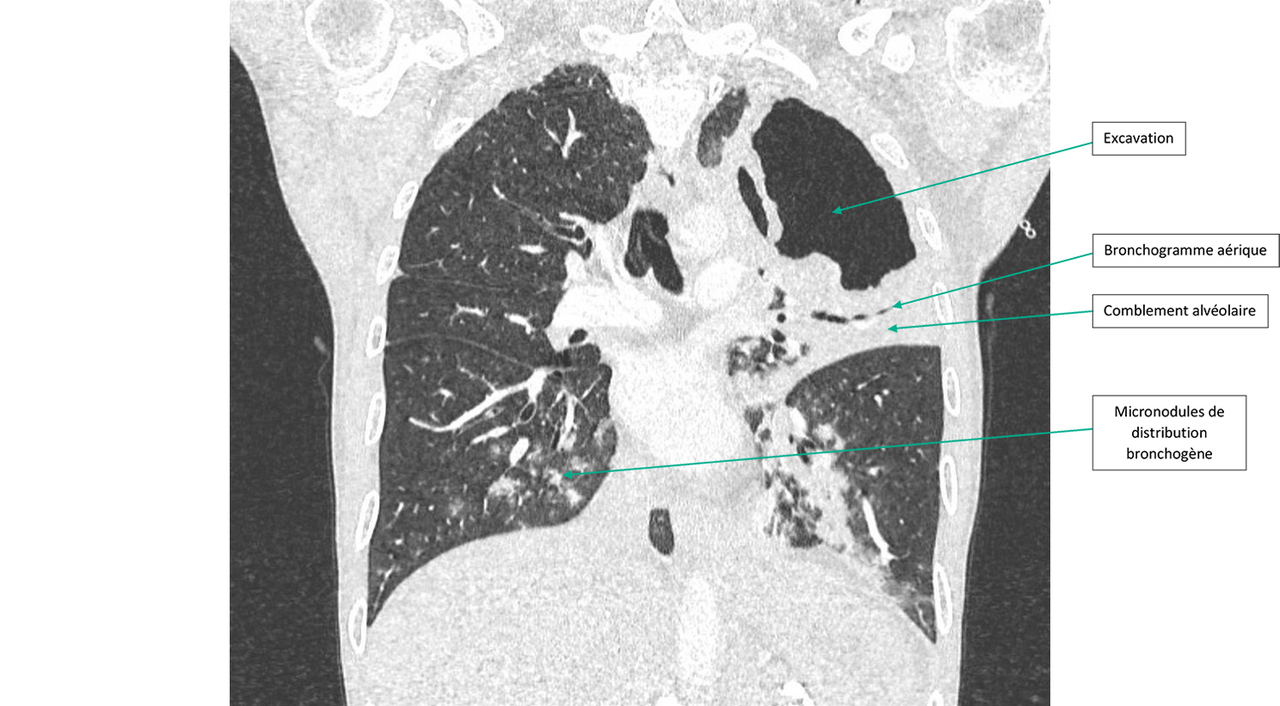

Un angioscanner thoracique est réalisé aux urgences devant les D-dimères élevés.

Figure 1 (Ariane Amoura, La Revue du Praticien)

Question 1 - Quelle(s) anomalie(s) observez-vous sur ce scanner ?

Il a une caverne du lobe supérieur gauche.

Il y a une opacité systématisée sur lobe supérieur gauche avec bronchogramme aérique en son sein.

On retrouve aux deux lobes inférieurs des micronodules de distribution bronchogène dits « en arbre en bourgeons ».

Il s’agit d’un scanner du thorax en coupe frontale et en fenêtre parenchymateuse. On ne retrouve pas d’embolie pulmonaire mais on observe une lésion excavée lobaire supérieure gauche de grande taille avec une condensation alvéolaire péri-lésionnelle avec bronchogramme aérique. Dans les lobes inférieurs, il y a des micronodules centrés sur des bronches (distribution bronchogène ou en arbre en bourgeons).